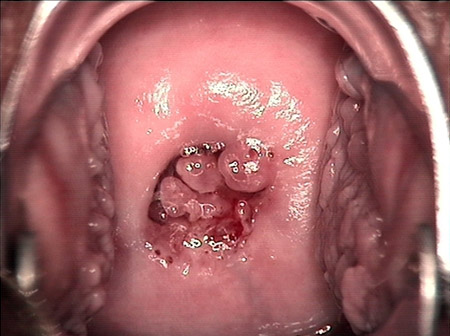

婦科leep錐切手術 CIN2-3

• CIN 2-3 碘著色后CIN 2-3 碘著色后